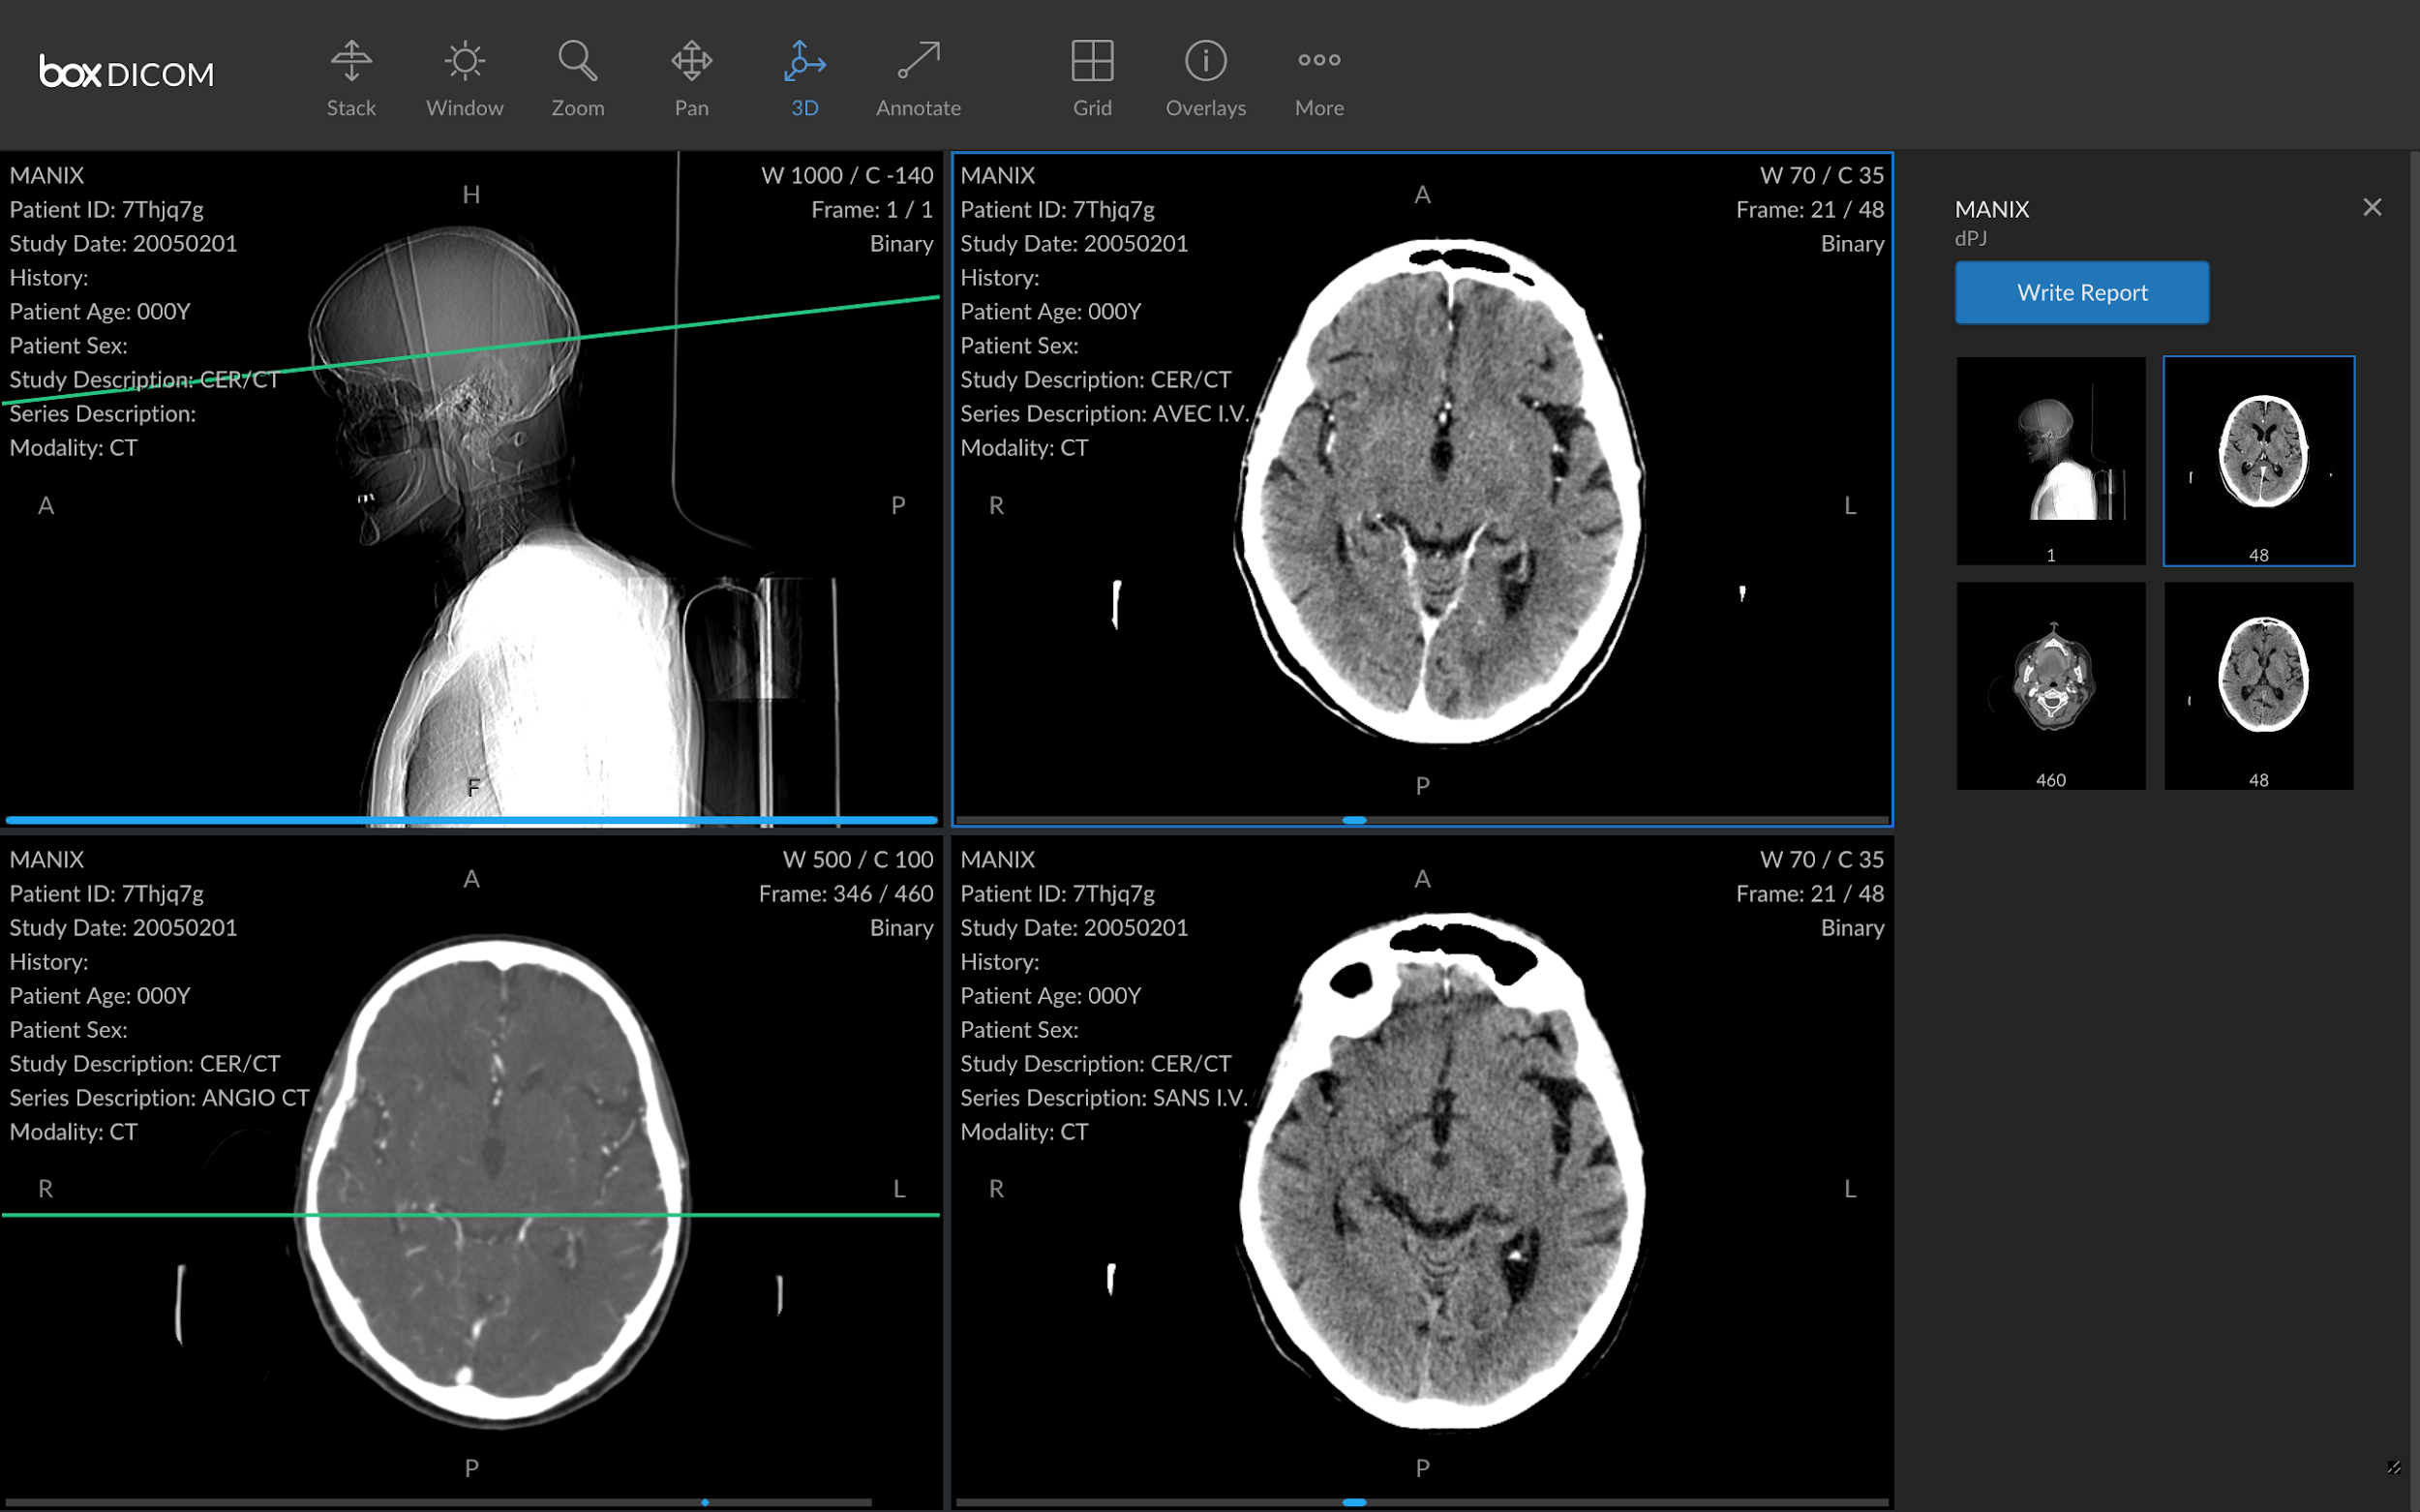

DICOM, acronyme de "Digital Imaging and Communications in Medicine" (Imagerie numérique et communication en médecine), est bien plus qu'un simple format de fichier. C'est un standard international qui régit la manière dont les images médicales sont acquises, stockées, partagées et affichées. Ce standard a vu le jour dans les années 1980, fruit d'une collaboration entre l'American College of Radiology (ACR) et la National Electrical Manufacturers Association (NEMA), face à la multiplication des systèmes d'imagerie incompatibles entre eux.

L'importance du format DICOM réside dans sa capacité à uniformiser les données d'imagerie médicale provenant de sources diverses. Qu'il s'agisse d'une radiographie, d'un scanner, d'une IRM ou d'une échographie, le format DICOM garantit que les informations soient lisibles et exploitables par les différents acteurs du parcours de soin, quels que soient le fabricant de l'équipement ou le logiciel utilisé.

Aujourd'hui, le format DICOM est devenu incontournable dans le secteur de la santé. Il facilite non seulement le travail des professionnels en leur offrant un accès rapide et fiable aux données médicales des patients, mais il contribue également à améliorer la prise en charge et le suivi des patients.